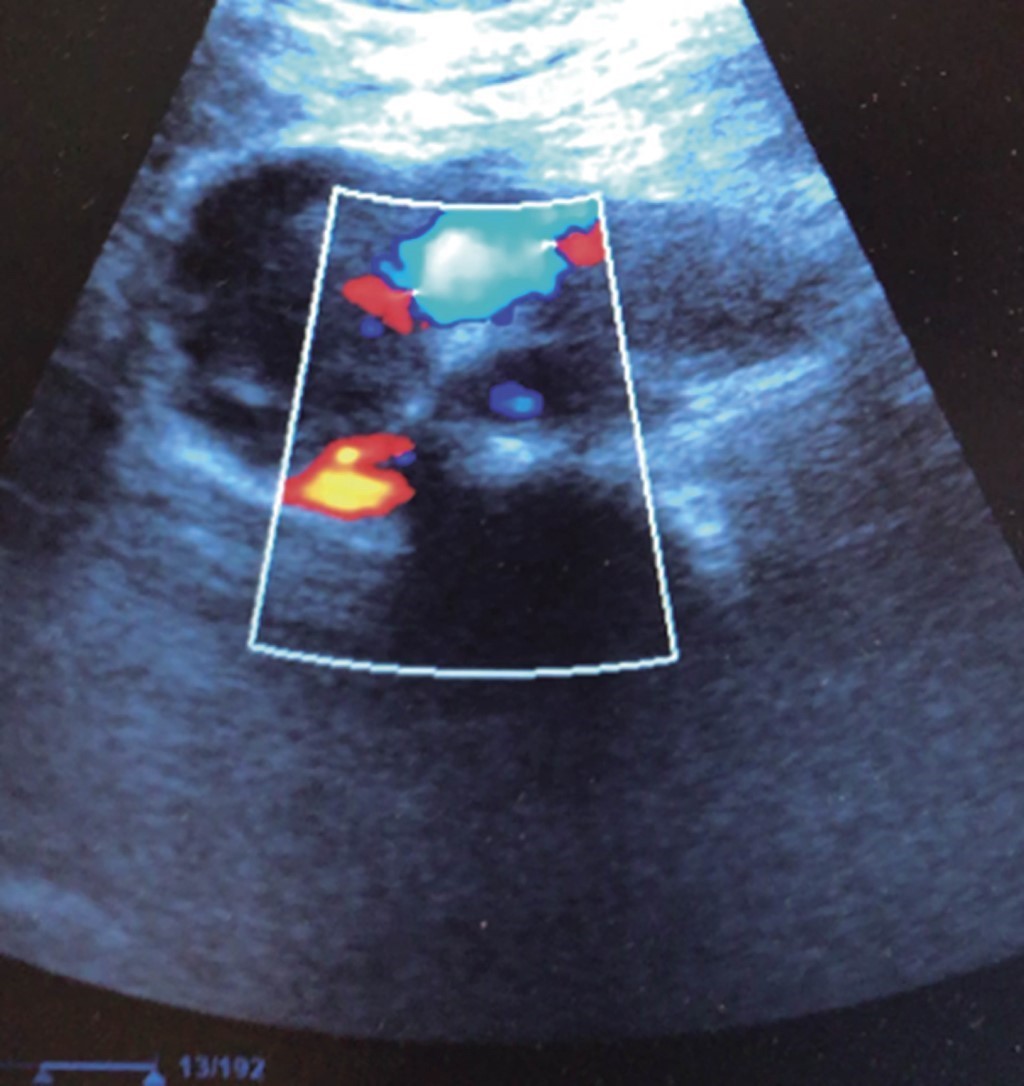

Un hallazgo incidental es cualquier fenómeno indeterminado detectado durante un examen que no tiene relación directa con el síntoma que motivó la exploración, pero que puede tener relevancia clínica que sugiera exámenes o interconsultas complementarios.22 Es para el cirujano general, habituado a recibir pacientes con malestares digestivos, encontrar la abrumadoramente común "distensión abdominal". "Es mi colitis, doctor" dicen los pacientes, y de cuando en cuando hemos encontrado sorpresas de trascendencia vital como tumores renales, una nodulación intravesical que resultó ser un carcinoma de células transicionales (Figura 6), o metástasis hepáticas (Figura 7), aneurismas de la aorta abdominal,23,24 o trombosis de la vena femoral, entre otros. El hallazgo incidental más frecuente en nuestra práctica es el hígado graso,25 que puede ser el detonante de un diagnóstico temprano de un síndrome metabólico y facilitar los exámenes y la orientación clínica pertinente para intervenir con oportunidad en este trastorno endémico. Son comunes los quistes simples, hepáticos o renales. En tales casos se miden su diámetro, se confirma la ausencia de contenido heterogéneo o flujo sanguíneo en su interior (Doppler) y, sobre todo en los renales, que no sustituyan al parénquima renal normal (como en la poliquistosis renal familiar). En ausencia de estas características, se le confirman al paciente como quistes simples y no ameritan mayor intervención. El parénquima hepático puede observarse interrumpido en su ecogenicidad habitual por algún fenómeno anormal como los adenomas o los hemangiomas, que no tienen mayor trascendencia clínica; pero ante cualquier nodulación hepática, debemos registrar la imagen y solicitar una opinión experta, y enviar al paciente al servicio de imagenología y que se protocolice mediante ultrasonido y/o TAC contrastada. Estos hallazgos permitirán profundizar en estudios que confirmen los diagnósticos y reorientar el abordaje terapéutico con una oportunidad que una simple palpación nunca hubiera conseguido y el paciente siempre agradecerá un examen con tal objetividad.

Figura 7